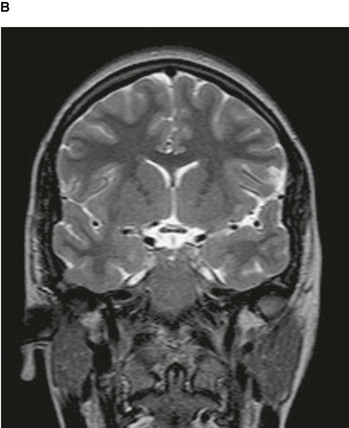

By altering the sequence of pulses to which the protons are subjected, different properties of the protons can be assessed. These properties are referred to as the “weighting” of the scan. By altering the pulse sequence and the scanning parameters, T1-weighted images (Fig. 1.10A) and T2-weighted images (Fig. 1.10B) can be obtained. These two types of imaging sequences provide differences in image contrast, which accentuate and optimize different tissue characteristics.

image image

Fig. 1.10 T1-weighted (A) and T2-weighted (B) magnetic resonance images of the brain in the coronal plane.

From the clinical point of view:

image Most T1-weighted images show dark fluid and bright fat—for example, within the brain the cerebrospinal fluid (CSF) is dark;

image T2-weighted images demonstrate a bright signal from fluid and an intermediate signal from fat—for example, in the brain the CSF appears white.

MRI can also be used to assess flow within vessels and to produce complex angiograms of the peripheral and cerebral circulation.